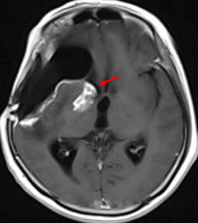

一例是两次复发三次手术的蝶骨嵴-海绵窦脑膜瘤。患者9年经历三次手术,最后一次手术术前影像提示肿瘤侵犯海绵窦,第三次术后复查磁共振提示肿瘤切除干净,然而出院后2周复查的磁共振发现术侧有异常病变影。三次手术的多灾多难,好歹隔了9年,这次仅仅两周,难道瘤子越来越恶了?

红色箭头指示的地方是出院后两周新出现的“阴影”、“结节”。

经过多个专业的专家会诊后,结合DWI,灌注,波谱等,前面病例考虑为急性局灶性梗死可能性大,后者考虑治疗后改变可能。当然,虽然患者听到这些话长舒一口气,医生们还是更为谨慎,定期复查或者更频密复发,必要时行PET-CT检查都是有必要的。